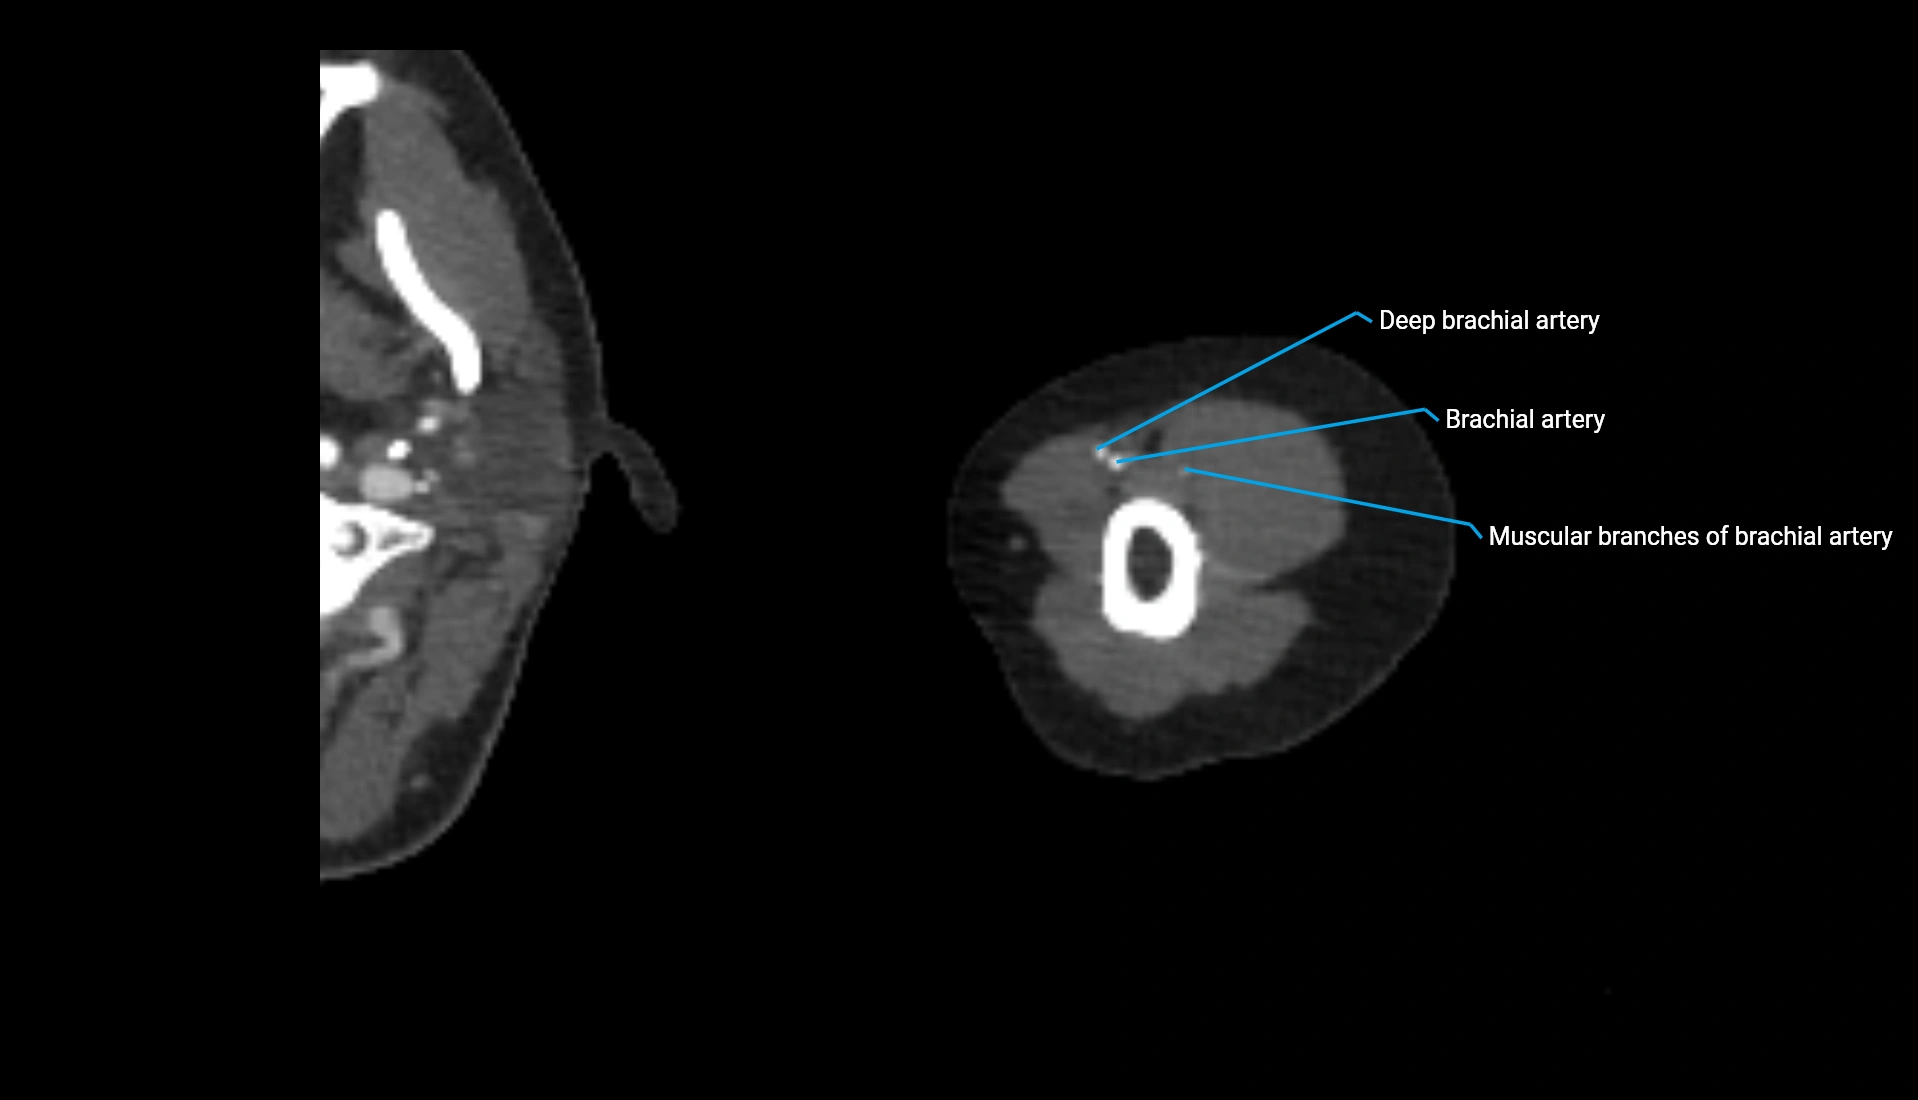

CT Appearance

Non-Contrast CT:

• Cortex: High-density, sharply defined

• Subchondral bone: Dense cancellous matrix

• Articular surface: Smooth concave contour articulating with the capitellum

• Excellent for evaluating bone integrity, alignment, and subtle fractures